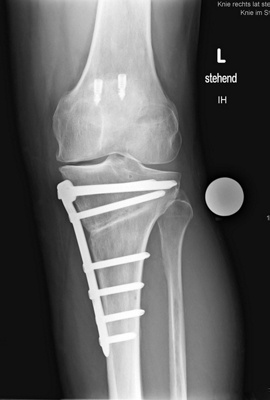

Dr. med. Alexander Strehl: Bei der häufigsten Umstellungsosteotomie am Unterschenkelkopf macht man einen Sägeschnitt am Knochen, klappt diesen gezielt auf und fixiert ihn mit einer winkelstabilen Platte; dies auf Basis dessen, was man vor der Operation bei der Planung gemessen und errechnet hat. Es entsteht ein winkelförmiger Spalt im Knochen, der von selber wieder zuwächst. Je nach Ort und Art der Deformität findet auch der Eingriff statt. Bei einem O-Bein ist dies meistens am Unterschenkelkopf. Es können aber auch Eingriffe am Oberschenkel nötig sein, vor allem beim X-Bein. Bei extremen Deformitäten kann auch eine Doppelosteotomie erforderlich sein, also dass man am Ober- und Unterschenkel korrigieren muss, um wieder eine gerade Achse zu erhalten. Dies muss man im Vorfeld genau analysieren und planen. Während der Operation wird die Beinachse mehrfach mit dem Ausrichtestab überprüft.

Bei Patienten ohne Voroperationen dauert der Eingriff unter zwei Stunden. Bei Voroperationen und vorhandenen Vernarbungen dauert es eventuell länger, da es schwieriger ist, alles zu lösen, um den Knochen aufzuklappen. Eine Doppelosteotomie dauert drei bis vier Stunden.